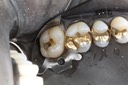

Wes Sato #30 prep